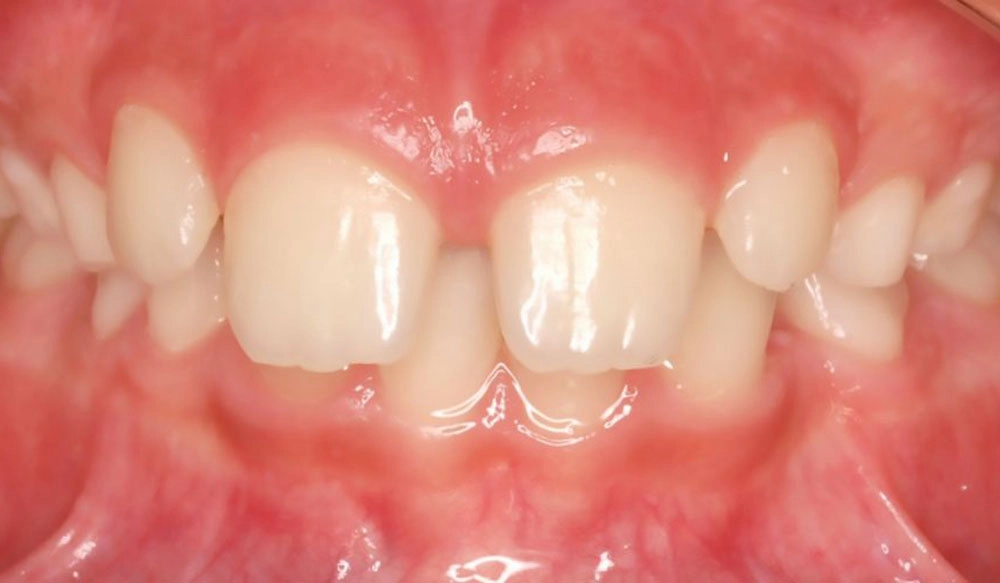

Spacing

Spacing — or “gap teeth” — is the condition in which there is excessive space between adjacent teeth in the dental arch.

Patient Information:

Age: 29

Gender: Male

Invisalign Treatment Option: Invisalign Go

Total Treatment Time:

7 months